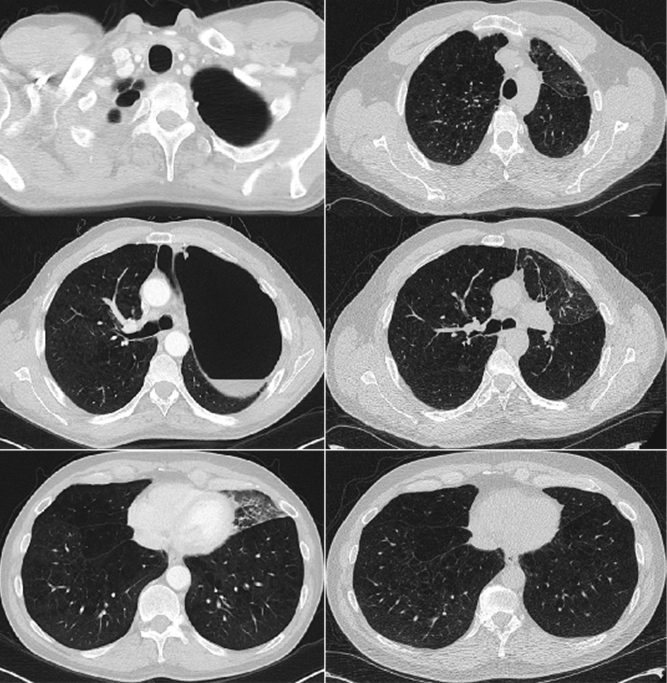

A 59-year-old male with chronic obstructive pulmonary disease (COPD) returned to the pulmonary clinic three-years after initial evaluation for bronchoscopic lung volume reduction for a giant left upper lobe bullae. He had moderately severe COPD (FEV1 1.6L, 37%) controlled on inhaler therapy and a greater than 35-pack/year smoking history. Previously, he was deemed a candidate for lung volume reduction. However, declined and was lost to follow-up (Figure 1). On presentation, he denied any decline in his physical capacity for the past three-years. His repeat chest CT scan demonstrated complete resolution of the large left upper lobe bullae. As a result of these findings, we did not recommend any further intervention with regard to the previous bullae. However, recommended annual lung cancer surveillance with low-dose chest CT scan.

Figure 1: Chest computed tomography scan at the level of the upper lobe, carina, and lower lobes. A very large left upper lobe bulla is observed (left) with spontaneous resolution after three-years follow-up (right).